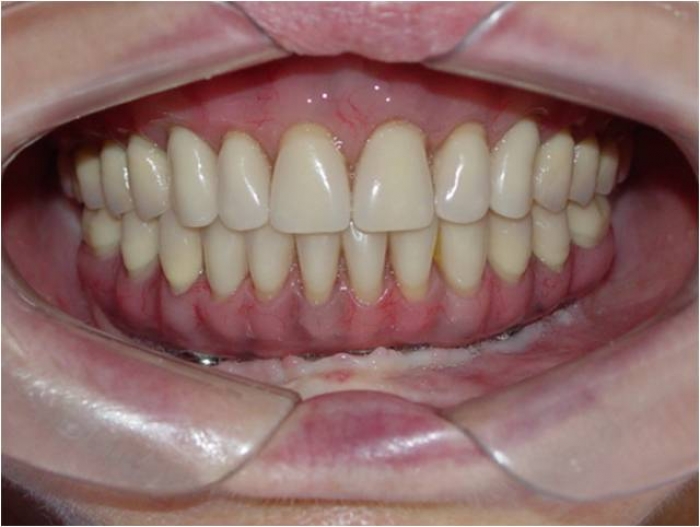

Prótese fixa inferior em resina

Sorriso final do caso terminado em abril de 2009